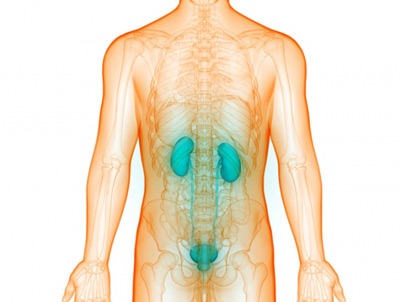

بیشتر بخوانید »نکاتی برای حفظ سلامت مثانه

مثانه از جمله اندام هایی در بدن انسان است که به طور معمول تا زمان بروز مشکل در آن کمتر مورد توجه قرار می گیرد. این در شرایطی است که پیشگیری از مشکلات مثانه بسیار آسانتر از درمان آنهاست. مثانه اندامی انعطاف پذیر است که زیر کلیه ها و پشت استخوان لگن قرار گرفته است. در یک دستگاه ادراری سالم، …